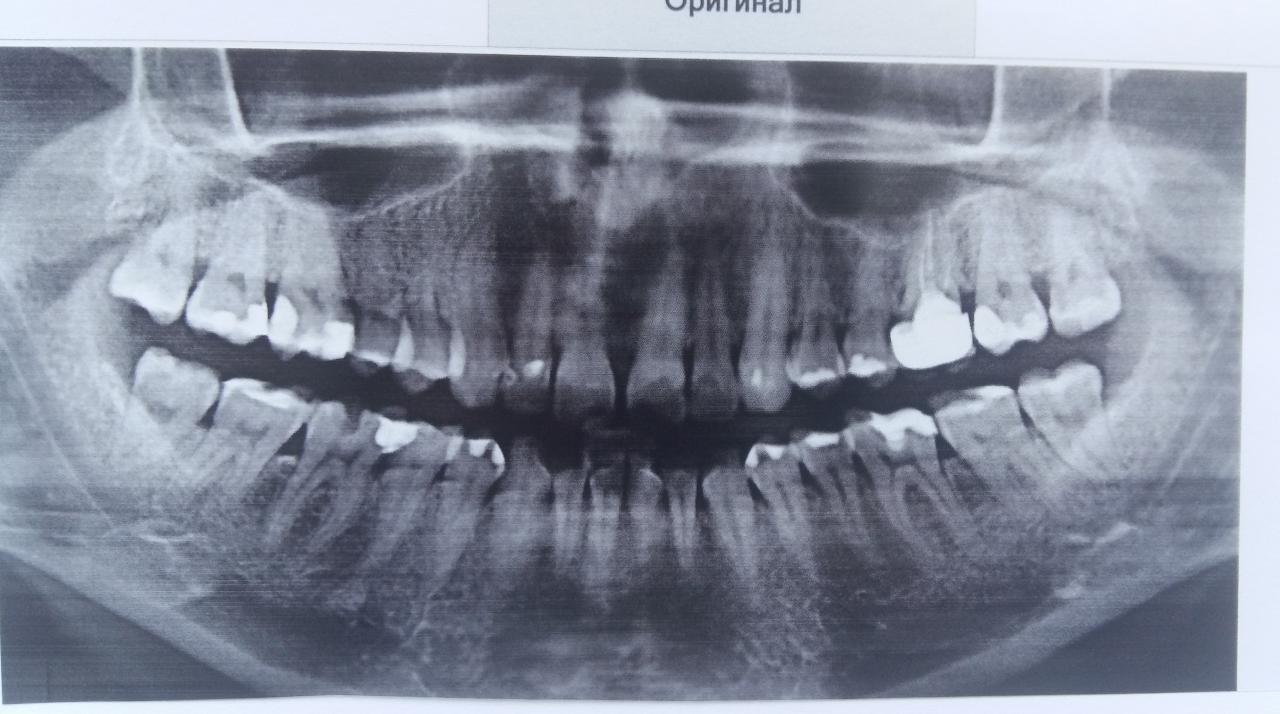

В январе появилось какое-то образование на десне (как сосудистое), небольшое, до 2 мм. Немного кровоточит. Гноя и других признаков воспаления нет абсолютно, не болит. Мой стоматолог удалил его поверхностно, но к концу марта оно опять появилось. Сейчас кровоточивости почти нет. Делали снимок зуба - мой врач в зубе проблемы не видит, направил к пародонтологу. Пошла к парадонтологу, сделали панорамный снимок; врач не него глянула и назначила время, когда прийти на лечение (диагноз и какое именно лечение не озвучила).

Подскажите, пожалуйста, видны ли какие-то проблемы на прилагаемом снимке ? (фото снимка делала на белой бумаге)

...явных проблем не наблюдаю (хотя, качество снимка желало быть лучшим), картина межзубных промежутков свидетельствует о наличии пародонтита/пародонтоза. Зуб под коронкой выглядит "не очень", но тут, скорее всего, будет стоять уже "до последнего" и удаляться...